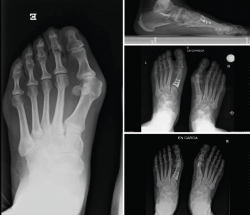

No se objetivó ningún caso de metatarsalgia de transferencia ni de pseudoartrosis. En las Figuras 2 y 3 se pueden ver detalles quirúrgicos de las osteotomías de apertura y cierre.

En las Figuras 4 y 5 se muestra un ejemplo intervenido de osteotomía de apertura y cierre.

Figura 4. Caso clínico de osteotomía de apertura medial (radiología preoperatoria y control a los 6 años y 8 meses).